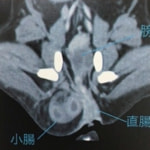

■ 症例 雑種猫 1歳 去勢雄

トイレにいる時間が長く、1回の排尿量が少ないとの主訴で来院。エコー検査にて、膀胱内に多量の微細砂粒を認めました。また、カテーテルが尿道の途中から入っていかず、砂粒が原因による尿道閉塞を起こしていることが確認されました。カテーテルから生理食塩水を注入することにより、詰まった砂粒を膀胱内に押し戻し、一時的に尿道閉塞を解除、尿検査の結果、微細砂粒はストルバイトと診断しました。食事療法および膀胱炎に対する対症療法を開始しましたが、連日尿道閉塞を繰り返すことから、会陰尿道瘻術を実施しました。術後は尿道閉塞の再発は無く、食事療法の継続で経過は順調です。